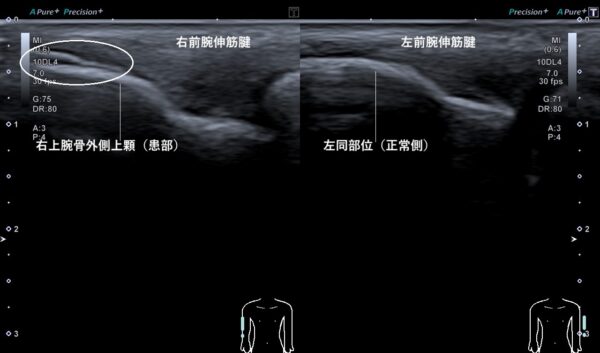

そこで、超音波(エコー)画像観察を行うと、右上腕骨外側上顆に付着している前腕伸筋腱の一部が剥離していました(画像、丸の中の白線が二重になっている箇所)。